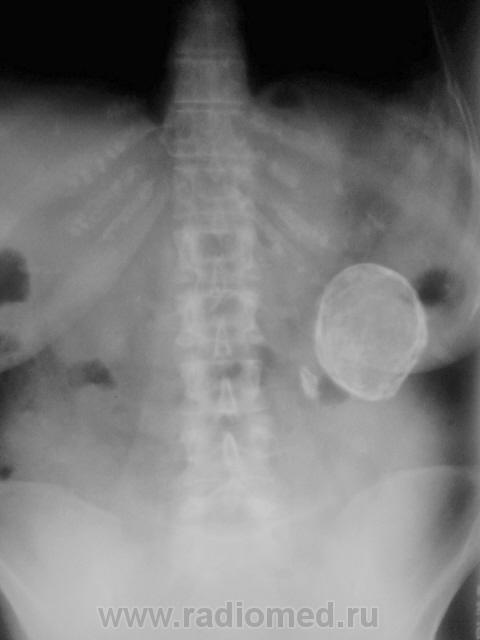

Больше данных за обызествленную кисту неясного генеза.

Обезыствленная полость в почке в сочетании с нефросклерозом. Помимо эхинококка нельзя исключить и обезыствленную туб. каверну. Туберкулез тоже, как известно, любит кальций.

Вполне м.б. закрытой эхинококковой кистой почки (или не почки) в сочетании с камнем. Возможно, у меня богатая фантазия, но, что за тень бобовидной формы слева на уровне Th12 - L1? Из опыта знаю, результаты УЗИ иногда лучше не принимать во внимание.

По снимку данное образование находится в проекции почки , правая-то хорошо визуализируется. А слева?

Интересно, а что, это, рядом с такой "каменюкой", маленькая "каменючка"?

"Младший братик" в синусе почки!

Тогда, выходит допустимо, предположить, что "булыжник" в почке, в лоханке?

Ребра тоже с известью... Склонность к кальцинозу. А не эхинококк? Протокол УЗи вызывает огромное сомнение в квалификации врача...

Один из коллег, ранее, высказал предположение, что имеет место, быть эхинококк селезенки.